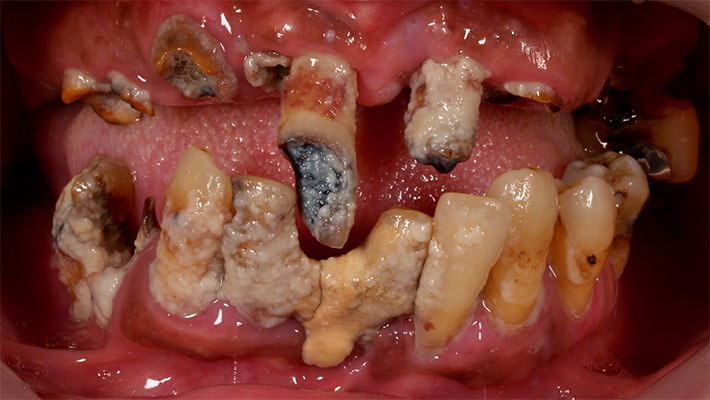

術前写真

全顎に渡り歯周病、カリエス(虫歯)、根尖性歯周炎等が進行し、歯を保存する事が困難である。